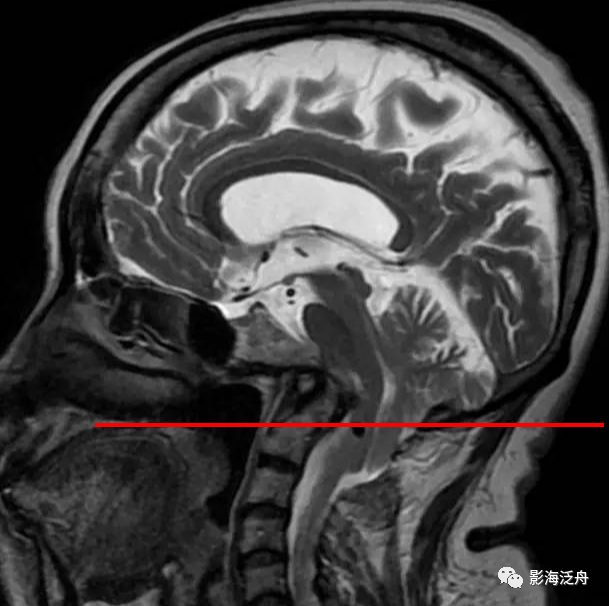

钱氏线

钱氏线:硬腭后缘与枕骨大孔后上缘的连续.

齿状突高于钱氏线9.6mm 齿状突高于斜坡延长线 克劳指数约2.

术前测量 adi=4.39mm 齿状突尖高于钱氏线7.83mm 斜坡齿突角=106.25

颈椎生理曲度变直,齿状突向上后方移位,超过硬腭与枕骨大孔下缘连线约

正常齿状突位于斜坡延长线下方斜坡延长线:如此线相交于齿状突基底部